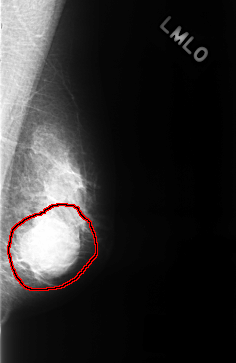

C_0323_1.LEFT_MLO

LEFT_MLO LINES 4352 PIXELS_PER_LINE 2824 BITS_PER_PIXEL 12 RESOLUTION 50 OVERLAY

FILE: C_0323_1.LEFT_MLO.OVERLAY

TOTAL_ABNORMALITIES 1

ABNORMALITY 1

LESION_TYPE MASS SHAPE ROUND MARGINS OBSCURED

ASSESSMENT 4

SUBTLETY 5

PATHOLOGY BENIGN

TOTAL_OUTLINES 1

BOUNDARY